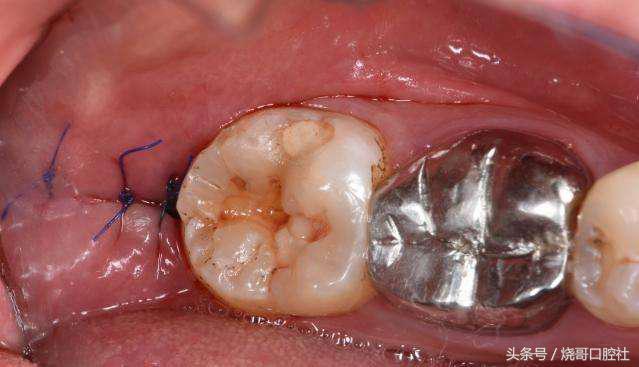

拔牙后是可以不用拆线的!比如羊肠线可以免拆,自动被牙龈组织吸收,但普通缝合线不可吸收,一般在5~7天内进行拆线处理,如果不及时拆线,要关注缝合线和牙龈长在一起,细菌会刺激牙龈发炎红肿,甚至引起口腔溃疡。

3、如果创口是智齿位置,那有可能会引起干槽症,明显拔牙后3~4天创口痛感会更加强烈,而且缝合线附近溃疡有异常的暗灰色,有时还能感觉到臭味。

既然是致病菌感染引起,就得再用重头清洗的方式,用生理盐水冲洗创口,特别是牙槽骨壁,再添加过氧化氢溶液反复来回清理,最后放入一个碘仿纱条,这样才会长出新的肉芽组织,很快3个月左右牙槽窝就能慢慢愈合长平。